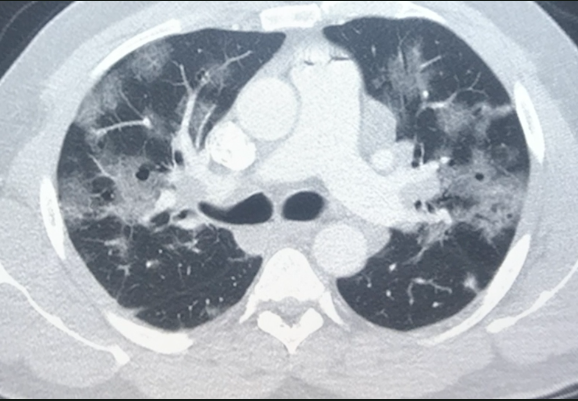

COVID-19 patient CT scan showing numerous ground glass lesions associated with SARS-CoV-2 pneumonia.